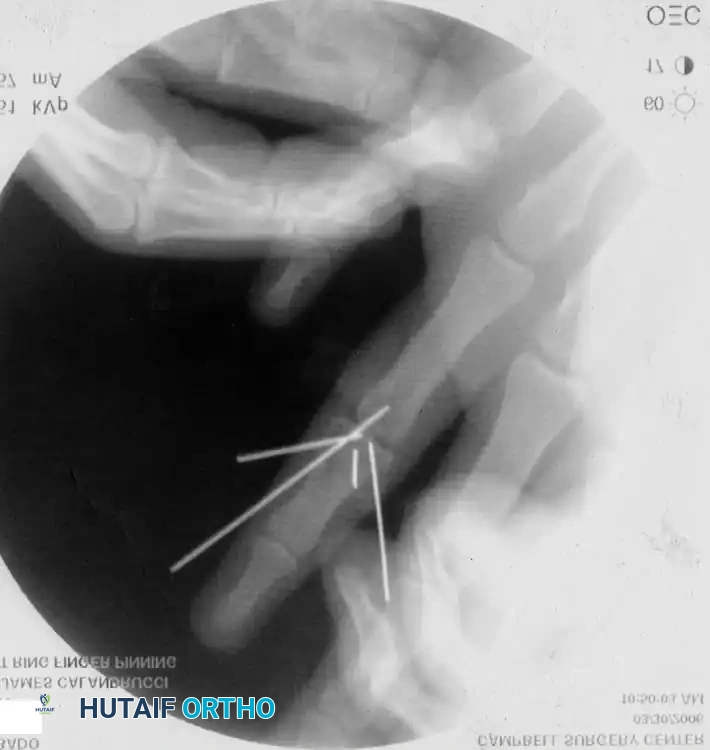

Percutaneous Techniques: Belsky-Eaton Pinning

Sometimes an unstable oblique fracture of a middle or proximal phalanx can be treated by closed reduction and percutaneous pinning. Belsky and Eaton described a highly effective technique for pinning multiple proximal phalangeal fractures without opening the fracture site.

Step-by-Step Technique:

* The fractured phalanx is held reduced with the MCP joint flexed to 90 degrees. This tightens the collateral ligaments, using them as a tension band to align the proximal fragment.

* A single K-wire is drilled from the dorsal aspect of the metacarpal head, passing across the MCP joint and straight down the medullary canal of the proximal phalanx to cross the fracture.

* Crucial Step: The wire must not cross the PIP joint.

* Leave the wire exposed proximally (bent outside the skin) to allow for easy removal in the clinic at 3 to 4 weeks.